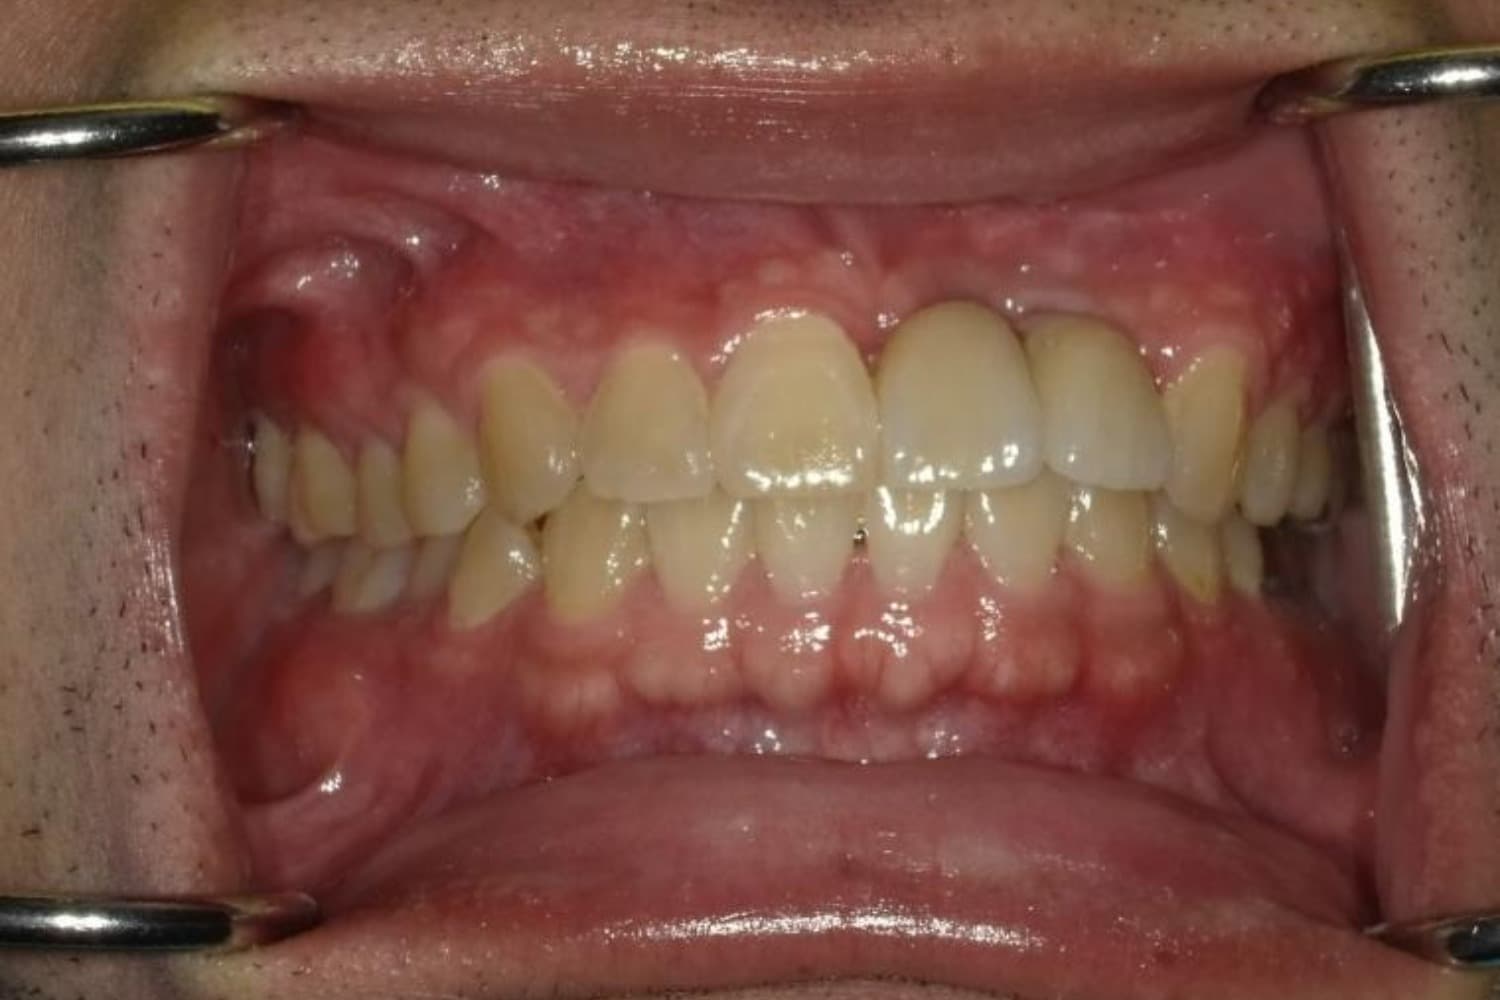

ガタガタとした歯並びや八重歯(1)

After

ガタガタとした歯並びや八重歯をマウスピース矯正(インビザライン)にて治療

主訴

下の前歯のガタガタが気になる

治療期間

2年5カ月

費用

90万円